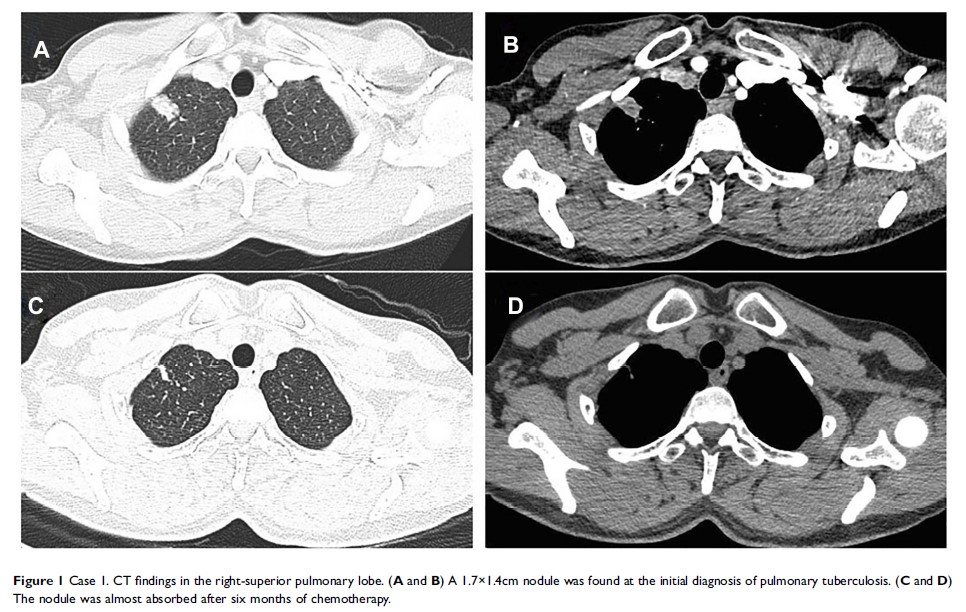

在抗结核治疗中,新肺部肿块形成时出现的反常反应:一个病例系列和文献综述